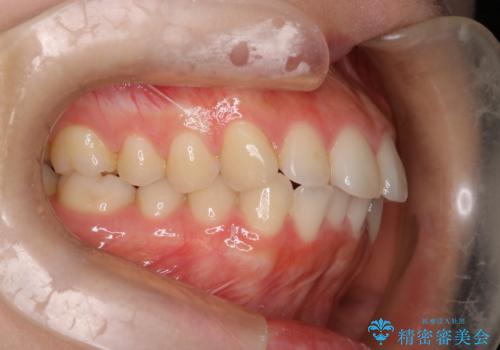

下顎前歯の叢生を短期間で改善

- 患者様は、下顎前歯のガタガタ(叢生)の改善を希望して来院されました。診断の結果、非抜歯で治療可能であると判断し、透明で目立たないインビザラインを使用する矯正治療計画を立案しました。短期間での治療を希望されていたため、IPR(歯間削合)を併用してスペースを確保しながら、効率的に歯を並べることを目指しました。

治療では、インビザラインを用いて計画的に歯を移動させ、短期間での歯列改善を実現しました。IPRを行うことで、抜歯をせずに必要なスペースを確保し、歯列全体を整えました。治療中は、装置の適切な装着時間を守ることが重要であり、患者様にも継続的な協力をお願いしました。また、歯肉や歯根への負担を最小限に抑えるため、歯の移動を慎重に管理しました。結果として、短期間で下顎前歯の叢生を改善し、自然な見た目と機能性を兼ね備えた歯列を実現できました。